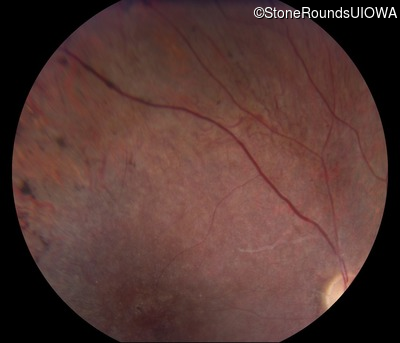

Fundus Photography - Right - 10/200

Exemplar